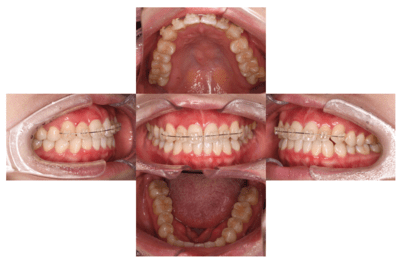

矯正中

【担当医師所見】

左右上下合わせて4本の抜歯を行った

①前歯もキレイに並んできました

②上の歯が外側になり、交叉咬合がなくなりました

③左上の出ていた歯を元の位置までもどしています